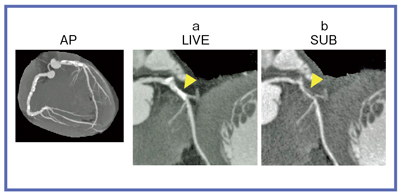

しかし,こうした課題は320列面検出器CTの登場により,解決の兆しが見えてきた。320列CTでは,心臓全体を1心拍で撮影し,ほぼ時相ズレのない画像を得ることができる。これにより,造影CTの情報から単純CTの情報を差分する“サブトラクション”,つまり,DSAと同様のデータを得ることが可能となった(図1)。

図1 320列CTによる著しい石灰化対策:冠動脈サブトラクションCT